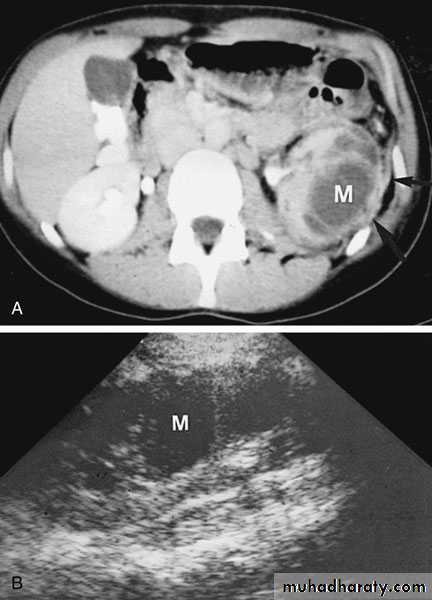

Chronic non specific infectionXanthogranulomatous Pyelonephritis

Rare, severe, chronic renal infection typically resulting in diffuse renal destruction.

Commonly affect middle age

Mixed bacteria: E. coli, Proteous mirabilis

Predisposing factors:

DiabeticRenal stone disease

Neurogenic uropathy

Obstructive uropathy

Clinical picture

ChronicLoin pain

Low grade fever & malaise

Weight loss

Renal mass

Multiple fistulae

Macroscopic appearance: Excessive fatty infiltration, Xanthene deposit

Investigations

GUE

KFT

U/S

CT scan

KUB

IVU

Treatment

Always surgery… NephrectomyUnder antibiotic cover